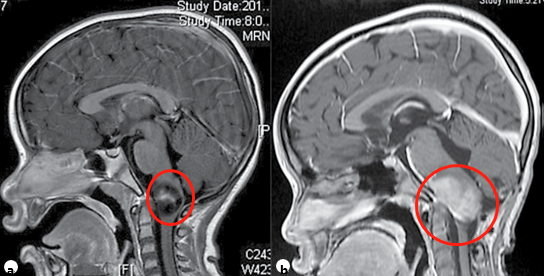

?。?)兒童頸髓膠質瘤典型表現為進行性共濟失調、下顱神經功能障礙。神經外科切除術在患者管理中起著重要作用,但應在較高精度的顯微神經外科手術設備和持續(xù)的術中神經生理學監(jiān)測條件下進行,目的是達到較大限度的順利切除病變。許多患者將需要術后化療和/或FRT(圖2)。此外,隨著時間的推移,患有此類腫瘤的兒童可能需要某種形式的枕頸穩(wěn)定。

兒童浸潤性頸髓腫瘤

圖2。一名7歲兒童浸潤性頸髓腫瘤的矢狀面造影后t1加權MRI (a)?;顧z和組織病理學診斷為低級別腫瘤,盡管使用化療(b)和FRT來治療控制腫瘤生長,但腫瘤仍在進展。